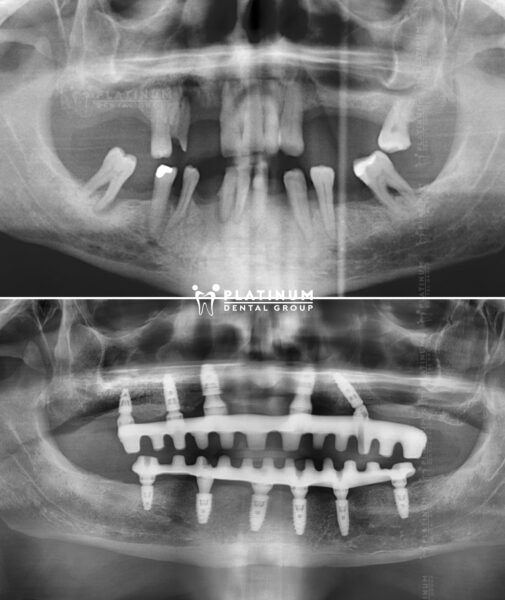

Mr Andrew “Lẽ ra tôi nên đến Platinum sớm hơn”

Tôi rất hạnh phúc với hàm răng mới, cảm giác tôi được là chính mình như lúc trẻ, có lẽ tôi nên đến Platinum Dental sớm hơn. Cảm ơn Platinum và bác sĩ đã cho tôi trở lại thật hoàn hảo.